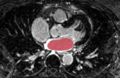

In the left image below (Figure R2), the manual segmentation of the endo-cardium is overlaid on the pre-op MRI. In the right image below (Figure R3), the same manual segmentation of the endo-cardium (of the pre-op MRI) is overlaid on the registered post-op MRI. This shows the registration accuracy around the endo-cardium region, which is the region of interest.